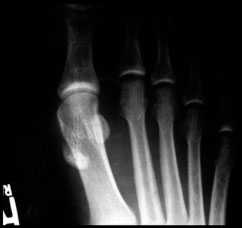

Рентгенограмма стопы в прямой проекции профессионального футболиста с признаками выраженной миграции сесамовидных костей.

При тяжелых повреждениях связок первого пальца выполняется стандартная рентгенография для исключения возможных костных повреждений, будь то отрывы капсулы сустава с костными фрагментами, переломы сесамовидных костей, расхождение или миграция сесамовидных костей.